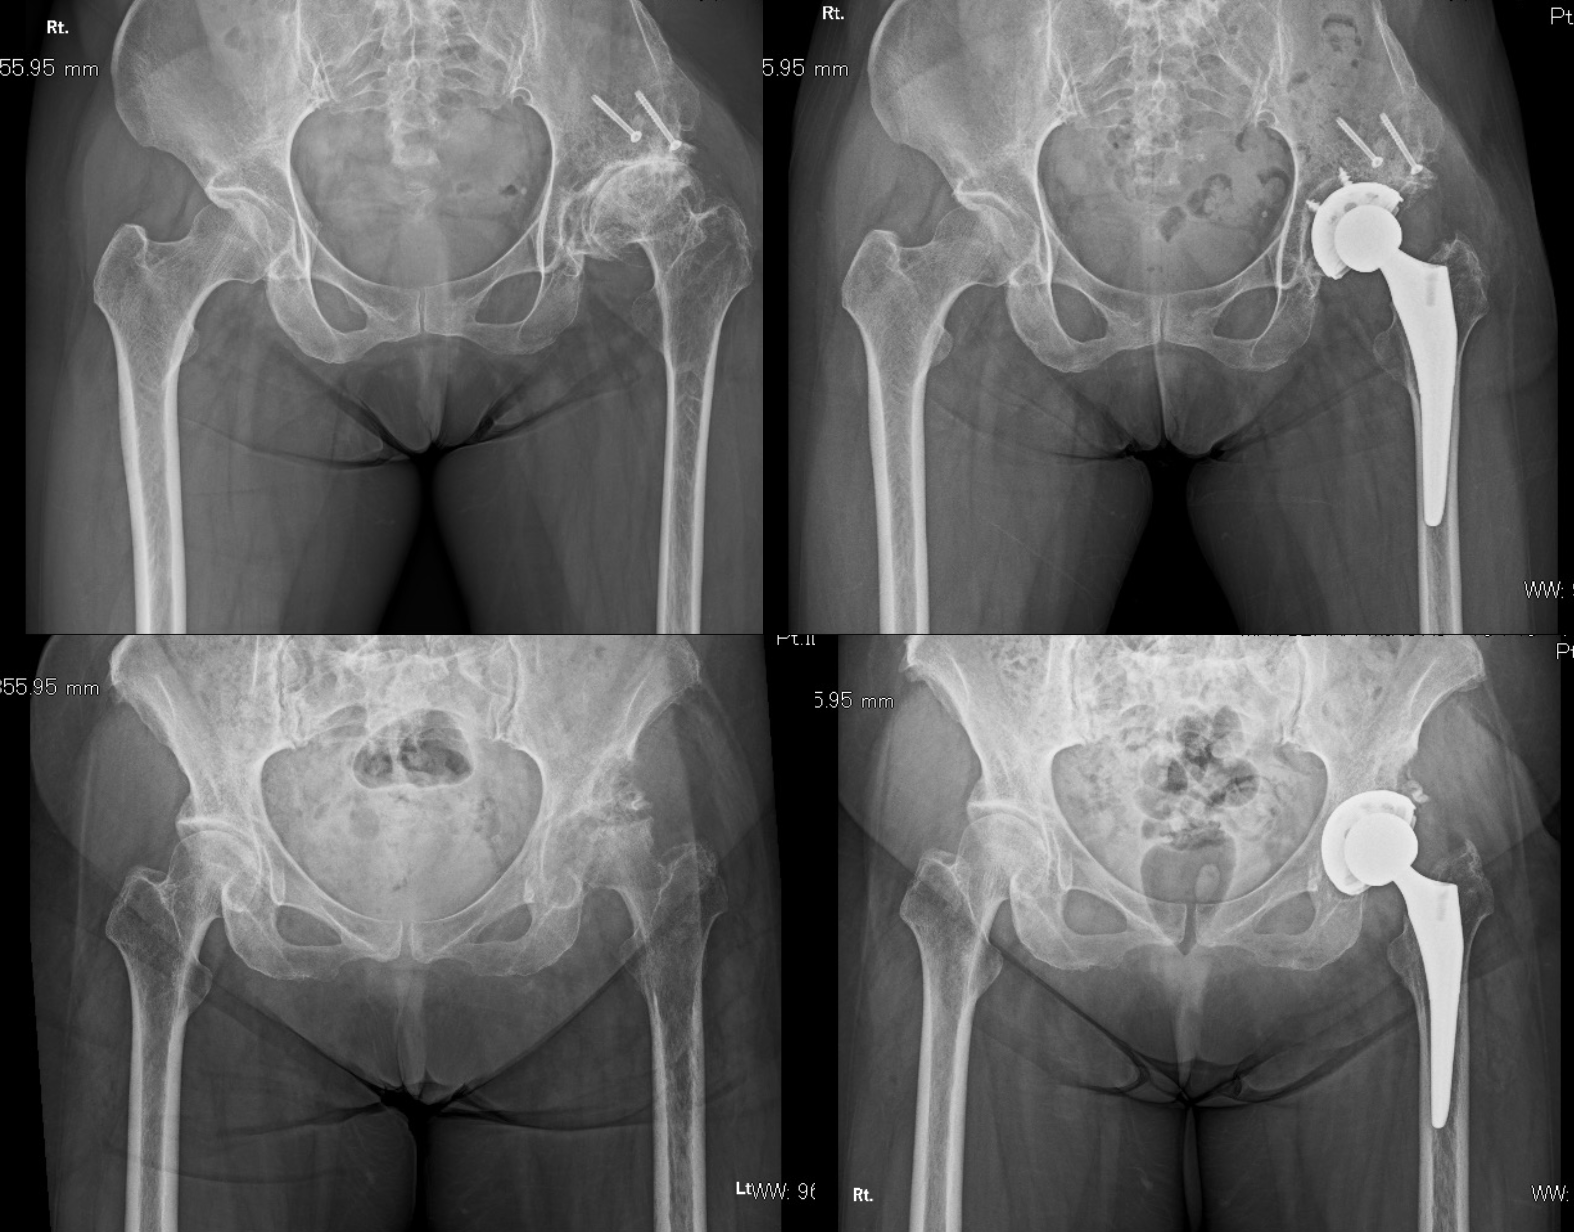

人工股関節置換術(Total hip arthroplasty、THA)では、術前のCT画像を基にコンピューターを用いた3次元術前計画を行います。その計画を詳細に検討し、ナビゲーションシステムを使用してSuperiorアプローチと呼ばれる従来の後方アプローチから派生したMIS(最小侵襲手術)を行っています(SuperPathもしくはDirect superior approach)。そのため術後の動作制限・禁忌肢位等は基本的に設けておらず、しゃがみこみ(squatting)、足を組むといった動作をゴールとしています。

また画像にあるようなシビアな症例でもしっかりと解剖学的・生理的に好ましい人工関節を設置することが可能です。